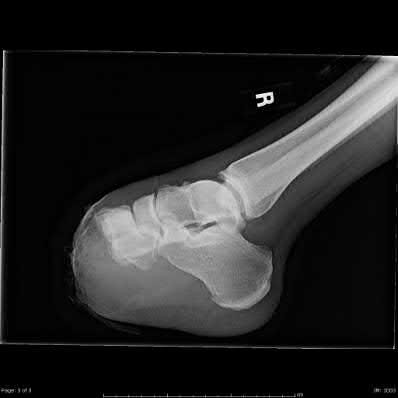

Question 8:

A 24-year-old football player sustains a high-energy hyperplantarflexion injury to his midfoot. Weight-bearing radiographs suggest a subtle Lisfranc injury. Which of the following anatomic descriptions accurately characterizes the primary strong band of the Lisfranc ligament complex?

Correct Answer: It connects the medial cuneiform to the base of the second metatarsal

Explanation:

The Lisfranc ligament is an oblique, interosseous ligament that originates on the lateral aspect of the medial cuneiform and inserts on the medial aspect of the base of the second metatarsal. It is critical for midfoot stability because there is no direct intermetatarsal ligamentous connection between the bases of the first and second metatarsals.